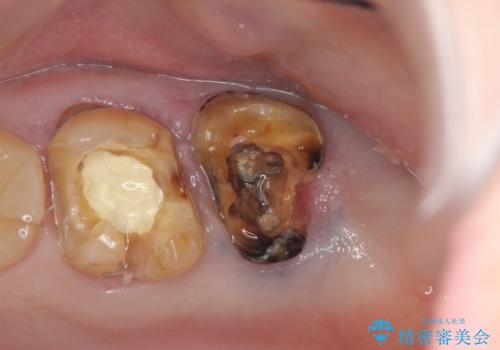

- 半年前から奥歯から嫌な臭いがする、と治療を求めて来院されました。

銀歯を除去したところ、虫歯が大きく再発しこのままではかぶせ直しができないような状況でした。

・深い虫歯 →歯周外科を行うことで歯ぐきの腫れを改善

・根尖性歯周炎 →精密根管治療